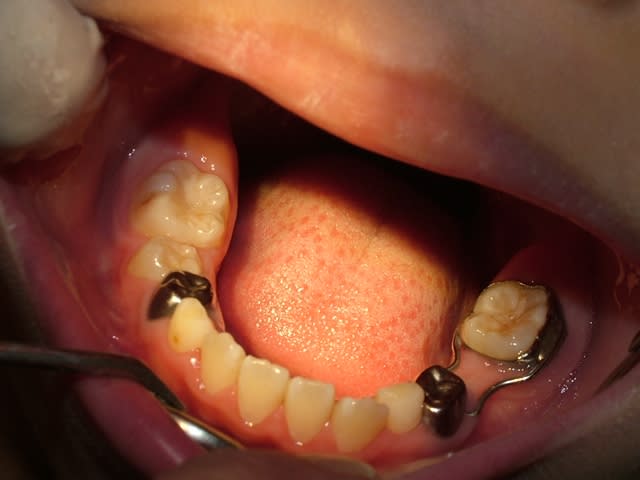

ds la mme,je récupère le frère

kelly:3 ans et 4 mois

Enfin, comme on dit mieux vaut tard que jamais!! J'ai vu un petit comme ça en vac de pédo au centre de soins, 3 ans et demi, le père a laissé tomber au bout de 2 séances... C'est tellement égoïste je trouve de la part des parents de laisser leur gamin comme ça! Ceci dit je suppose que comme ça s'est bien passé avec antoine, ils vont faire la totalité des soins avec le petit, c'est déjà ça :)

Bon, vu la photo, je suppose que t'as des extractions et une petite prtohèse amovible prévues?

pr sig,les extractions st faites,les soins aussi,une couronne pedo est prévue en fevrier et la prothèse amovible pas faite: je n'ai pas de prothesiste pedo sur place et je ne suis pas persuadée qu'il va la porter